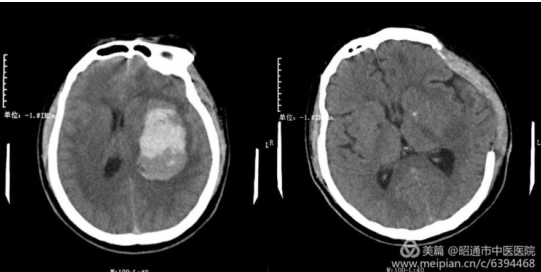

一患者因"突发右侧肢体偏瘫伴失语3小时"送入我院急诊科,入院时血压 177/118mmHg,神志嗜睡,不能对答,查体不完全配合。肿瘤科急会诊后收住入院,但家属拒绝手术,要求保守治疗。两日后,患者病情加重,神志昏迷,左侧瞳孔散大固定,直径约7mm,对光反射迟钝,急查头颅CT后提示:左侧基底节区出血灶范围较入院增大,左侧侧脑室受压较入院明显。李主任紧急召开了病例讨论,在征得家属同意后决定立即行去颅骨瓣减压术+脑内血肿清除术。术后患者双侧瞳孔大小恢复正常,对光反射敏感,并转入我院重症医学科进一步治疗,后经我院中医康复治疗,病情稳定好转出院。

治疗前 治疗后